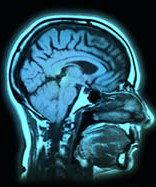

АЛС е нелечимо заболяване на нервната система, което разрушава клетките, отговорни за волевите движения. АЛС понякога се нарича заболяването на Lou Gehrig - по името на известния бейзболен играч, починал от него.

Заболяването обикновено поразява хора между 40 и 60 годишна възраст, като е по-често срещано при мъжете. За съжаление няма много данни за факторите, които го предизвикват.